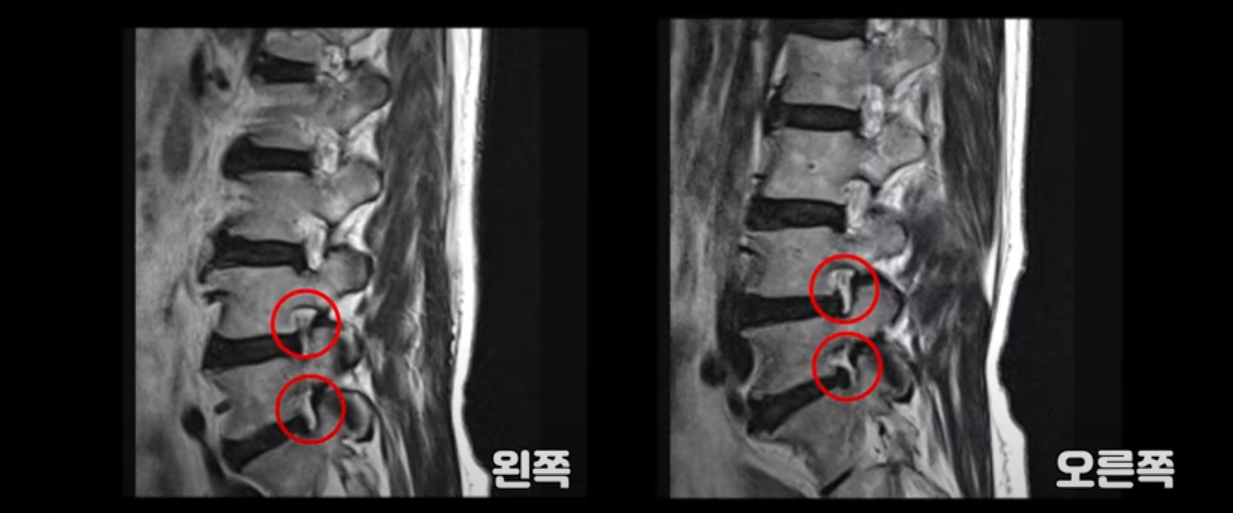

이 환자분 MRI 보면서 설명 드린 후 왜 이런 환자는 신경주사가 효과가 없는지 왜 근육재활치료를 꼭 받아야 하는지, 근육재활치료로 어떻게 좋아질 수 있는지 설명 드리도록 하겠습니다. 이분MRI를 보면 허리 여러 마디 퇴행이 진행되어 있고 디스크와 협착도 있지만 아주 심해 보이지는 않습니다.

이분 다리는 양쪽이 다 아픈데 양쪽 추공간이 좁아져 있긴 하지만 여전히 하얀 지방이 많이 보이는 상태로 심하게 좁아 보이지는 않습니다.

척추관이 가장 좁아진 4번 5번을 보면 중심성 협착이 있지만 많이 심하지는 않습니다